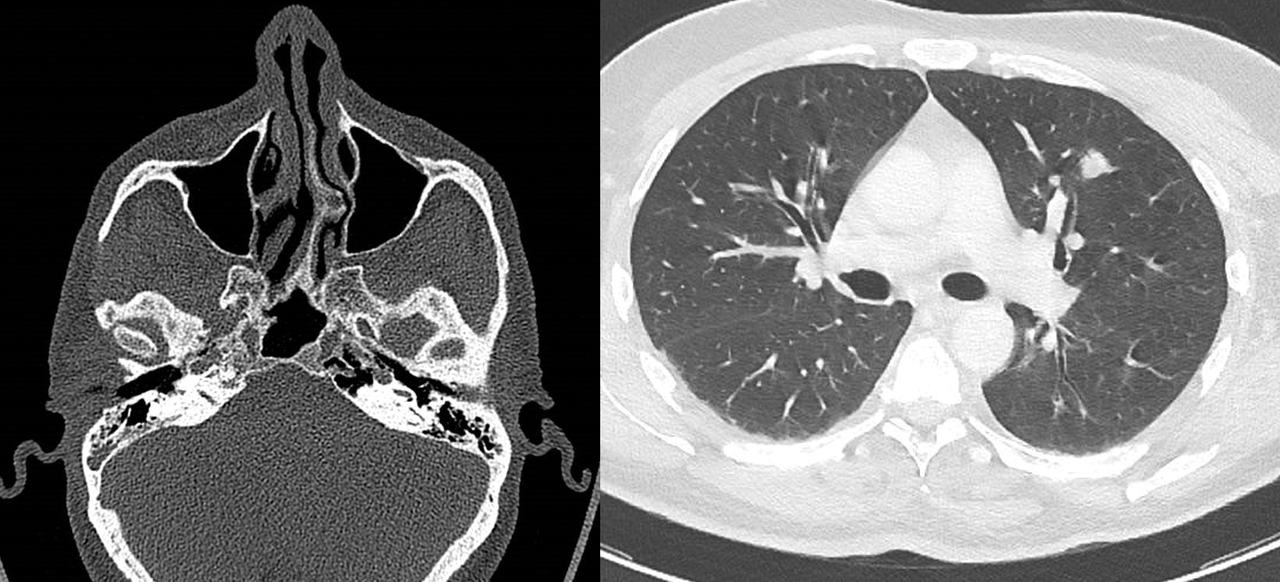

Le scanner montre un comblement des cellules mastoïdiennes et un nodule pulmonaire. La CRP est à 125 mg/L. Il a une protéinurie et une hématurie à la bandelette urinaire.

La granulomatose avec polyangéite (GPA) est une vascularite des petits vaisseaux caractérisée par des symptômes ORL trainants (sinusites, otites), une atteinte pulmonaire (nodules, infiltrats, hémorragies alvéolaires) et une glomérulonéphrite extracapillaire. La présence d’anticorps anticytoplasme des polynucléaires (ANCA) de type protéinase 3 est très évocatrice. Le traitement associe corticoïdes, cyclophosphamide ou rituximab.